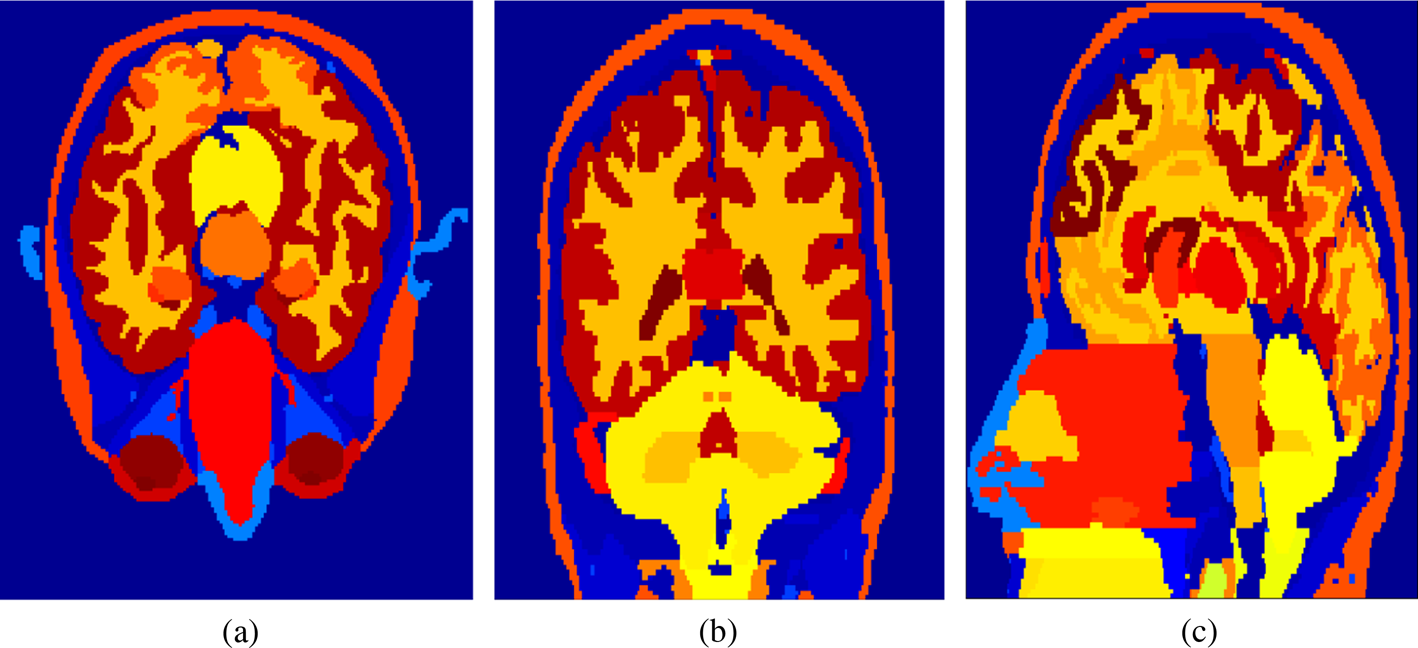

Human-head model

A realistic human-head model proposed in [Reference Zubal, Harrell, Smith, Rattner, Gindi and Hoffer37] is used in this work. The dimensions of the head model are 172 × 218 × 240 mm3. The head model is divided into 73 million cells whose sizes in all directions are 0.5 mm. Thus, the total cell number of the FDTD problem space with 10 CPML cells and 10 air gap cells on all sides is about 100 million.

The head model consists of eight tissues: skin, fat, bone, eye, blood vessel, muscle, white matter, and gray matter. The mass density [Reference Kaburcuk and Elsherbeni20], relative permittivity, and conductivity of the head tissues calculated from Debye coefficients in [Reference Kaburcuk and Elsherbeni20] and [Reference Eleiwa and Elsherbeni38] for 2.4 and 5.8 GHz are tabulated in Tables 1 and 2. Figure 3 shows the human-head model's x–y, x–z, and y–z cross sections.

Fig. 3. (a) x–y, (b) x–z, (c) and y–z cross-sections of the human-head model.